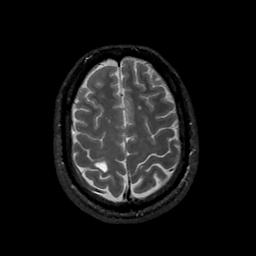

MR Study #11, May 5, 1991 -- Slice #40